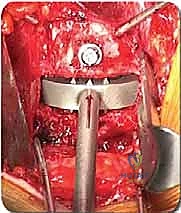

الخطوة 2: التعامل مع الأوعية الدموية (Vascular Mobilization)

هذه هي الخطوة الأكثر دقة. أمام العمود الفقري القطني توجد الأوعية الدموية الكبرى في الجسم (الشريان الأورطي والوريد الأجوف السفلي وتفرعاتهما). باستخدام أدوات دقيقة ورؤية مكبرة، يتم تحريك هذه الأوعية بلطف شديد لحمايتها وكشف القرص الفقري المستهدف (غالباً L4-L5 أو L5-S1).

الخطوة 3: استئصال القرص (Discectomy)

بمجرد كشف القرص، يقوم الأستاذ الدكتور محمد هطيف بإزالة المادة الغضروفية التالفة بالكامل. يتم تنظيف الصفائح النهائية للفقرات (Endplates) العلوية والسفلية بعناية فائقة للوصول إلى العظم النازف، وهي خطوة حاسمة لضمان نمو العظم الجديد والتحامه.